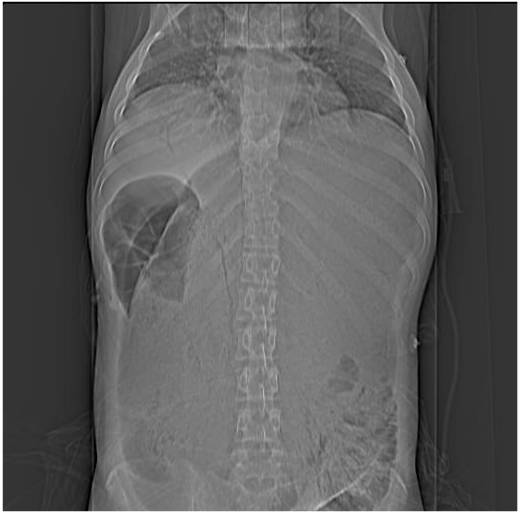

Image

Fig.10. Gastroplegia

An 18 years old bulimic female patient was admitted after eating a pot of lentil stew. She was immediately transferred to the operating room, but she died during the surgery. On the plain film the overtly distended stomach almost completely fills the abdominal cavity.